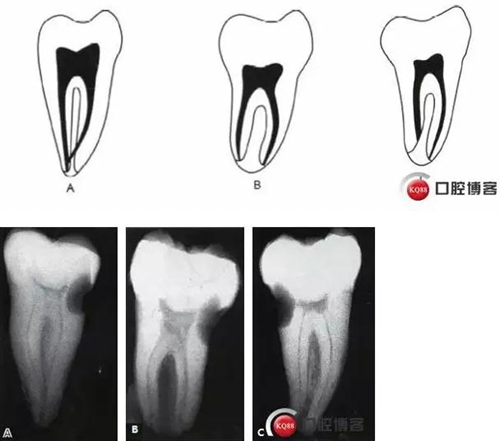

這種分類方法將下頜第二磨牙分為3 型:

I型:融合型,X線片上見2個根管,但在根尖區(qū)融合。

II型:分離型,X線片見2個根管且互相獨(dú)立。

III型:不對稱型,X線片上雖有2個根管互相獨(dú)立,但一長一短,互不對稱。

6.jpg